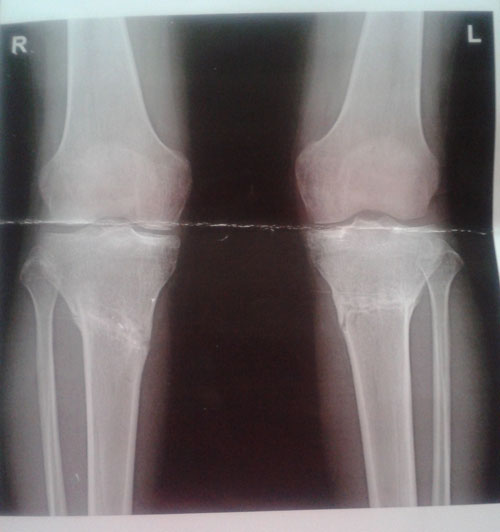

Рентген в 1,5 месяца после снятия аппаратов.

По рентгену сращение отличное, ось ровнейшая. Без ограничений, каблуки можно. Носите на здоровье!